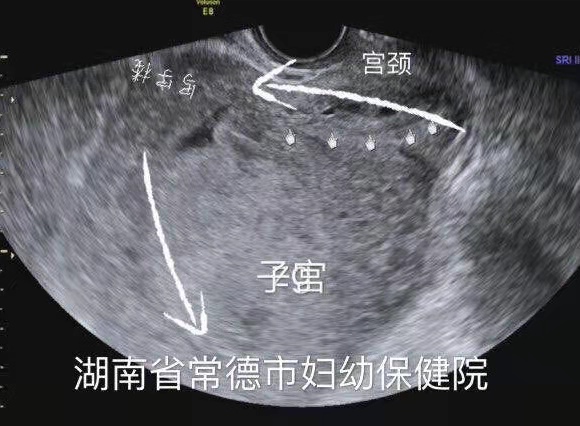

子宫明显后倾后屈,宫颈细长

尿潴留缓解,子宫位置已转前位,宫颈远离尿道